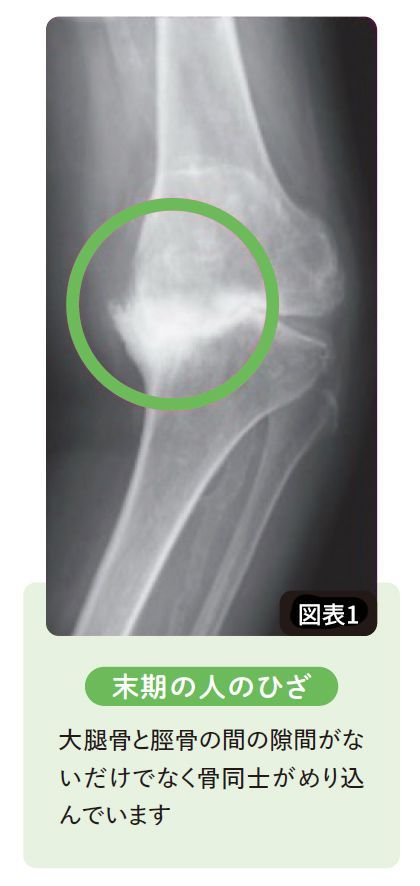

実際、変形性膝関節症の末期ともなると(図表1)、大腿骨が脛骨にめり込んでしまう「骨欠損」が起きます。

【図表】末期の人のひざ

出典=巽一郎『足腰復活100年体操』より

軟骨には知覚神経がないので、すり減っていく過程で軟骨自体から痛みは感じません。しかし中期以降、大腿骨と脛骨がぶつかるようになると、骨膜には知覚神経があるので、この頃から痛みは激痛に変わるのです。

1歩踏み出すごとに、激痛が走ることも稀ではない。ふつうは末期まで進行しません。ここまで進行してしまうのは、朝夕鎮痛薬を飲んで骨を削っていたからです。